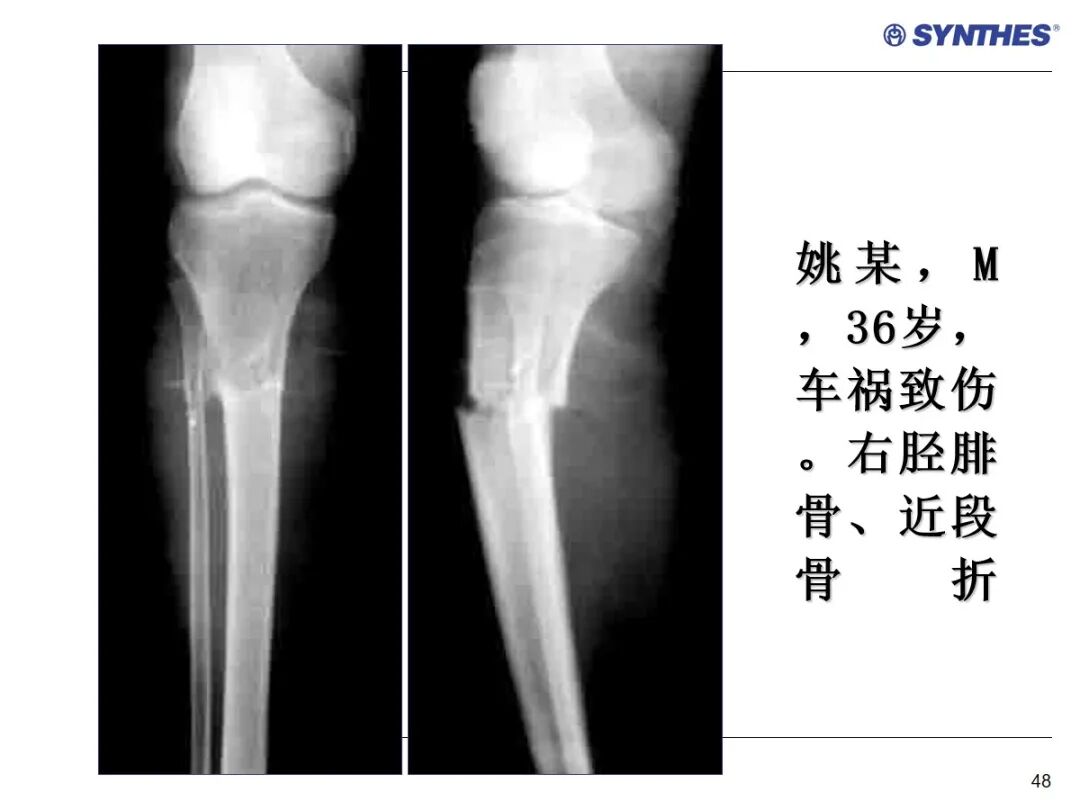

LISS微创固定系统应用技巧,原来如此简单!